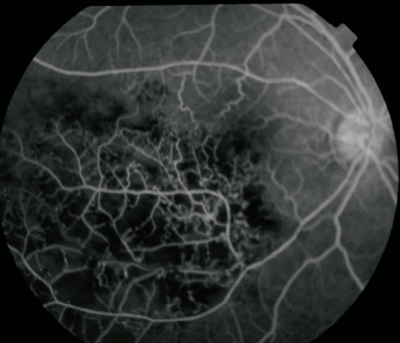

58歳の男性。1か月前からの右眼の視力低下を主訴に来院した。視力は右 0.1 (0.3 × -1.0 D)、左 0.7 (1.2 × -1.0 D)。眼圧は右 12 mmHg、左 11 mmHg。前眼部、中間透光体に異常を認めない。カラー眼底写真、蛍光眼底写真、黄斑部の光干渉断層計〈OCT〉像を別に示す。

この患者に対してまず行うべき治療はどれか。

d. 抗VEGF薬硝子体注射